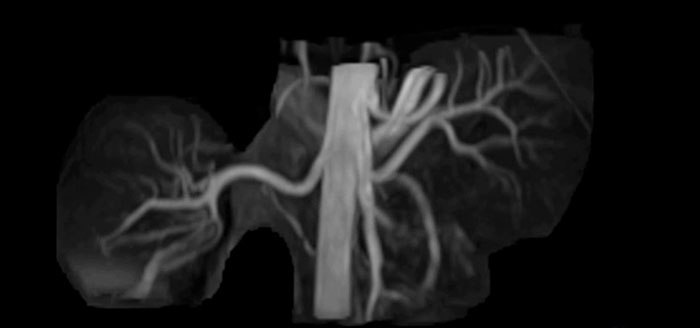

Positioning and operation: smooth and simple Once the scanner was in place, Mrs. Schiffer and her staff received tailored training in line with their clinical and workflow requirements and objectives. “I have been impressed from the start. Installation and set-up were smooth and simple. Within three days, our technologists were confidently using the new system,” recalls Mrs. Schiffer. Since installing Prodiva 1.5T, she and her team have noticed a number of enhancements to their daily work. The scanner’s simple Breeze workflow supports easy patient positioning with fewer positioning steps, rapid set-up and changeover times. Ultra-light anterior coils, short cables and small connectors are making technologists’ lives easier. Senior MRI technologist Sandra Maass says: “Speaking for myself and my colleagues, we all very much enjoy using Prodiva – and we benefit from its many workflow advantages every day.” And Mrs. Schiffer adds, “The flexible, lightweight coils fit really well to the patient’s body shape, and the connectors are superb: connecting and disconnecting requires just little effort.” “The shoulder coil is a great example of easy positioning with Prodiva,” says Mrs. Maass “Other shoulder coils can be quite rigid, so that patients with pain, or bigger stronger shoulders, or a somewhat abnormal shoulder or spine anatomy cannot be positioned well in the coil, which often leads to loss of image quality. However, the Prodiva shoulder coil is very flexible and has large coverage, which makes good positioning easier and that contributes to the superb image quality and high SNR that we get in our shoulder exams.” High quality of images impresses From a clinical perspective, too, Mrs. Schiffer is very impressed with Prodiva 1.5T. In her practice around 50% of scans are neurological, 40% musculoskeletal and the rest made up of vascular, abdominal and miscellaneous cases. The radiology team is receiving good results across anatomies, which their referring physicians are confirming to them. “Prodiva’s high image quality and advanced features, including diffusion-weighted imaging in many organs, improve our diagnostic confidence and help decision-making,” says Mrs. Schiffer. “Prodiva has been an excellent investment and is definitely the right choice for us.” “The quality of the contrast-free MR angiography keeps impressing us,” says Mrs. Schiffer. “In addition to not having to inject contrast agent, these images are amazing, for instance of the carotids. Also our exams of shoulders and hands are really exceptional. Images of the hands, for example, cover the fingertips and include the full wrist as well, all with high signal-to-noise ratio.”

Imaging the renal arteries without contrast agent on Prodiva 1.5T.